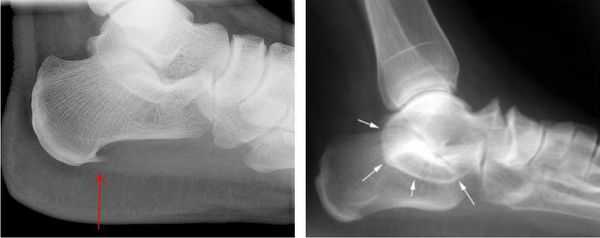

Диагностика

Для постановки окончательного диагноза применяется:

- рентгенография большеберцовой кости

- КТ

- денситометрия (определение плотности костной ткани)

- МРТ

Самым информативным методом диагностики, дающим объективную оценку состоянию всех близлежащих мягких тканей, надкостницы и кортикального слоя большеберцовой кости, признана магнитно-резонансная томография. Безопасная атравматичная технология позволяет дифференцировать шинсплинт от стрессовых переломов, воспаления сухожилия и хронического миофасциального синдрома.

При подозрении травматической природы синдрома проводится рентгенография голеностопного сустава и стопы. Во время исследования также можно обнаружить костные выступы и остеофиты.